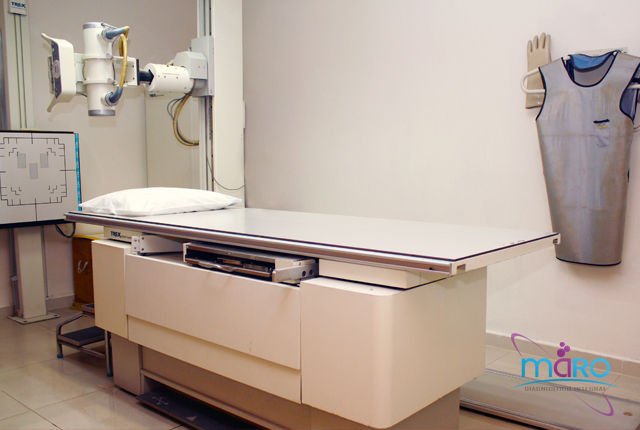

Más informaciónLaboratorio de análisis clínicos

- Serologías

- Hematología

- Inmunología

- Bacteriología

- Parasitología

- Tamizaje neonatal amplaido

- Prueba de paternidad